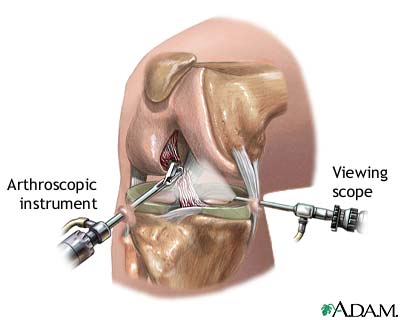

استفاده از میله داخل استخوانی به عنوان یک وسیله استاندارد برای فیکس کردن شکستگیهای ناحیه وسطی استخوان درشت نی است. در صورتی که شکستگی جابجایی داشته باشد و قطعات شکسته شده نسبت به هم حرکت کرده و جابجا شده باشند، درمان معمولاً به صورت عمل جراحی انجام میشود.

در این روش، بعد از ورود به اتاق عمل و تحت بیهوشی یا بیحسی، قطعات شکسته شده با استفاده از تکنیک جااندازی بسته به هم متصل میشوند. سپس پزشک معالج با ایجاد یک شکاف طولی چند سانتیمتری در جلوی زیر زانو، سوراخی در بخش بالایی استخوان درشت نی ایجاد میکند و میله داخل استخوانی را از طریق این سوراخ وارد کانال استخوان تیبیا (درشت نی) میکند. این میله در طول کانال استخوانی قرار گرفته و قطعات شکسته شده را در کنار یکدیگر قرار میدهد.

میله داخل استخوانی با دو پیچ در بالا و دو پیچ در پایین به استخوان درشت نی متصل و تثبیت میشود. تمامی این مراحل با استفاده از دستگاه رادیوگرافی به نام فلوروسکوپی انجام میشود و پزشک معالج با استفاده از اشعه ایکس و مانیتور دستگاه مراحل جااندازی و قرار دادن میله داخل استخوانی را کنترل میکند. این روش جااندازی بسته و تثبیت با میله داخل استخوانی به آن میگویند.

در موارد نادر، ممکن است نیاز به جااندازی باز باشد، به این معنی که با شکاف دادن پوست، قطعات شکسته شده قابل مشاهده شوند و با استفاده از ایزارهایی در کنار یکدیگر قرار داده شوند. اما پزشک معالج سعی میکند تا حد امکان از روش جااندازی بسته استفاده کند، زیرا این روش عوارض کمتری دارد و شکستگی زودتر بهبود مییابد.